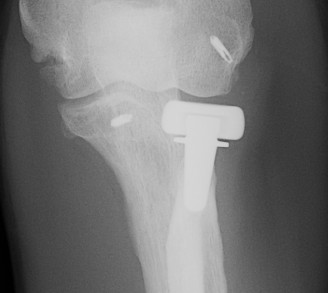

Overstuffing

| Lesser sigmoid notch | Symmetry of ulnohumeral joint |

|---|---|

|

Radial head shoulder articulate with lesser notch

Ensure no gapping of lateral ulnohumeral joint |

![]() |

- cadaveric study

- increased medial ulno-humeral joint line gapping with overlengthening of 6 or 8 mm

- increased lateral ulno-humeral joint line gapping with overlengthening of 2 mm